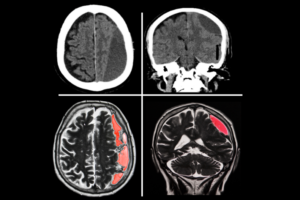

Beyin tümörü ameliyatı, tümörlü dokunun dikkatle çıkarılarak beyin fonksiyonlarının korunmasını ve hastanın yaşam kalitesinin artırılmasını amaçlayan ileri düzey bir cerrahi girişimdir.

Beyin ameliyatı, hastalığın türüne ve yerine göre mikrocerrahi yöntemlerle kafatasında açılan bir pencere aracılığıyla beyin dokusuna ulaşılarak gerçekleştirilen hassas bir cerrahi işlemdir.

Kronik subdural kanama, genellikle hafif kafa travmaları sonrası beyin zarları arasında yavaşça kan birikmesiyle oluşan ve baş ağrısı, dengesizlik, unutkanlık gibi belirtilerle ilerleyen ciddi bir beyin kanaması türüdür.